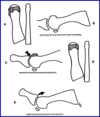

- Proximal phalanx osteotmy

- Kessel bonney

- resection of dorsally based wedge of bone from base proximal phalanx

- Regnauld “mexican hat”

- shortening osteotomy of proximal phalanx

- Kessel bonney

- 1st metatarsal osteotomy

- Watermann

- dorsal wedge trapezoid osteotomy out of 1st met head

- Watermann-Green

- piece bone removed from dorsal half of met head with second cut angulated to protect sesamoids

- Youngswick

- austin/chevron osteotomy with two parallel cuts dorsally

- allows lateral transposition

- Dorsal V

- chevron cut made dorsal to plantar through met neck

- Sagital Z

- sagittal z through met shaft with proximal arm exiting meditally and distal arm exiting laterally

- can lengthen or shorthen

- Lambrinudi (not jt destructive)

- plantarflexory base osteotomy to correct metatarsus primus elevatus

- Oblique sagittal base osteotomy

- cut through metatarsal base

- Watermann